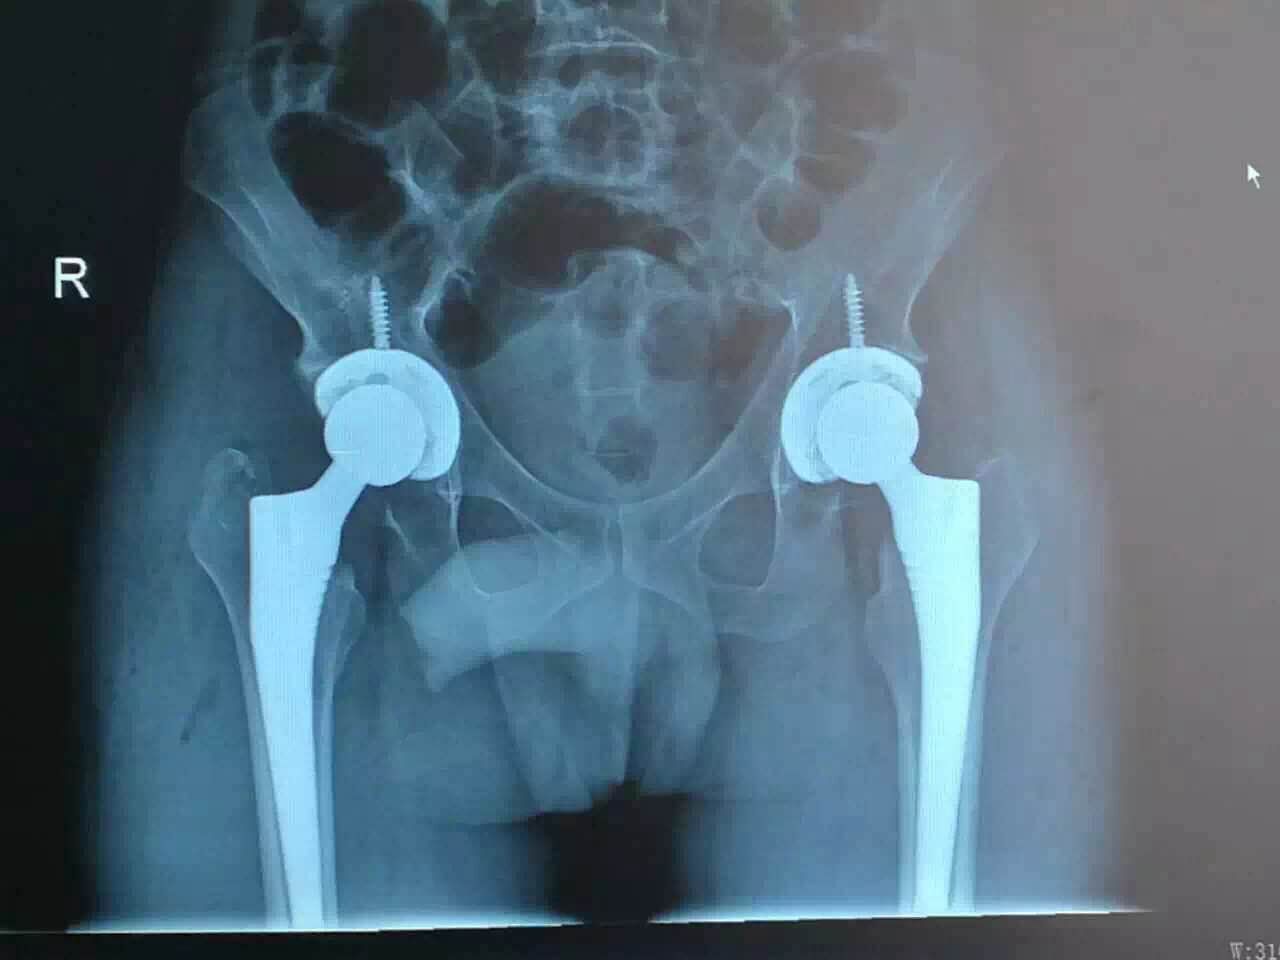

近日,我院骨科成功為一名老年男性患者實(shí)施“雙側(cè)股骨頭無(wú)菌性壞死”人工髖關(guān)節(jié)小切口DAA-THA置換術(shù),目前患者康覆出院,術(shù)后患者膝關(guān)節(jié)功能良好,對(duì)我院骨科精湛的技術(shù),人性化的關(guān)懷表示高度好評(píng)及感謝。

患者鄭某某,男性,55歲,笏石本地人。以“雙髖疼痛2年,加重伴活動(dòng)受限10個(gè)月”為主訴入住我院骨科?;颊呷朐呵?年因無(wú)明顯誘因出現(xiàn)雙側(cè)髖關(guān)節(jié)疼痛,在莆田多家醫(yī)院行雙側(cè)髖關(guān)節(jié)攝片提示:雙側(cè)股骨頭無(wú)菌性壞死。經(jīng)莆田多家三甲醫(yī)院行保守治療,患者雙側(cè)髖關(guān)節(jié)疼痛無(wú)明顯緩解。近一年來(lái),患者雙側(cè)髖關(guān)節(jié)疼痛漸加劇,漸出現(xiàn)雙側(cè)髖關(guān)節(jié)活動(dòng)受限,出現(xiàn)跛行,無(wú)法正常行走,無(wú)法正常下蹲大便,嚴(yán)重影響患者生活質(zhì)量?;颊咔皝?lái)我院求診于林群賢主任。林群賢主任詳細(xì)查體及閱片后,以“雙側(cè)股骨頭無(wú)菌性壞死”收入我科治療。因患者雙側(cè)股骨頭無(wú)菌性壞死,病程達(dá)兩年,目前雙側(cè)髖關(guān)節(jié)嚴(yán)重變性壞死,關(guān)節(jié)活動(dòng)消失,日常生活只能借助拐杖行走,長(zhǎng)期關(guān)節(jié)疼痛,嚴(yán)重影響日常生活及工作。經(jīng)我科林群賢主任醫(yī)師組織科室內(nèi)進(jìn)行討論后,決定行雙側(cè)人工全髖關(guān)節(jié)置換術(shù)。為減少住院時(shí)間、住院費(fèi)用、減輕患者術(shù)后疼痛,決定行小切口DAA-THA(關(guān)節(jié)置換術(shù))。完善相關(guān)術(shù)前檢查后,兩日后在腰硬聯(lián)合麻醉下行手術(shù)治療。手術(shù)時(shí)間3小時(shí)左右,手術(shù)過(guò)程順利,術(shù)中病人無(wú)其他痛苦及不適,手術(shù)出血少。術(shù)后患者下病房后,一個(gè)勁的說(shuō):以前一直害怕手術(shù),怕手術(shù)會(huì)痛,會(huì)出很多血,想不到這次手術(shù)這么順利,我就稍微睡了一下,手術(shù)就好了,而且一點(diǎn)也不痛苦,出血也少。感謝你們高超的技術(shù),盛興醫(yī)院“大厲害、大好果”。術(shù)后第二天,患者雙側(cè)髖關(guān)節(jié)疼痛明顯緩解,雙髖關(guān)節(jié)活動(dòng)度較前明顯改善,可以在座便器上正常大便,在助行器幫助下正常下地行走,跛行步態(tài)消失。術(shù)后9天,患者康覆出院。